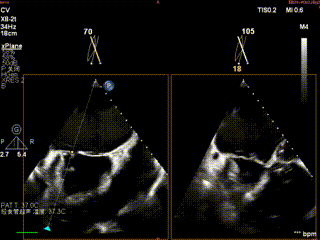

术前肺静脉频谱

怎么上穿刺鞘攻克巨大左房伴转位穿刺难关!温医大附一院周浩教授团队创新应用“导丝定位+可调弯鞘”技术完成高难度TEER手术_https://www.jmylbn.com_新闻资讯_第11张

1.二尖瓣重度关闭不全(4+),瓣环明显扩大(AP径4.6cm,LM径3.9cm),扁平,关闭时瓣叶对合不佳(carpentier I),1-3区均可见反流束,返流宽度达26mm;肺静脉频谱呈收缩期反向。